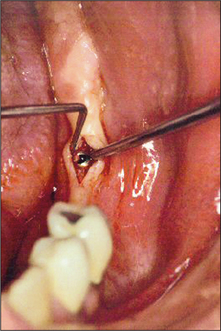

Second-stage surgery to expose an implant

After the healing phase is complete it can sometimes be difficult to determine the exact location of a two-stage (submucosal) implant. A dental probe can be used to palpate the cover screw through the anaesthetized tissues. Once the cover screw is located, a crestal incision is made to expose it (Fig. 11.30). The cover screw is then removed and a healing abutment inserted. If necessary, resorbable sutures are placed to ensure close apposition of the oral mucosa to the healing abutment (Fig. 11.31). After a period of 7–10 days, the healing abutment is replaced with a suitable abutment that will subsequently be loaded.

Fig. 11.30 Second-stage surgery. The cover screw is exposed via a small incision.